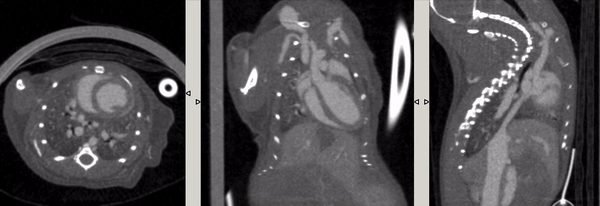

心跳門控:活體小鼠注射顯影增強劑Exitron 12000,超高時間分辨率(10ms),成像時間:2min40s。

心跳門控.gif